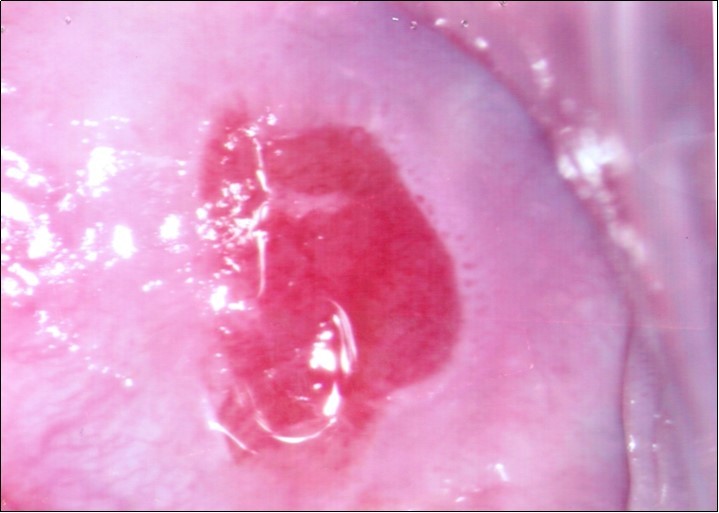

At initial presentation, colposcopy was unsatisfactory due to inadequate visualisation of the transformation zone. (Figure 1) Severe cervico-vaginitis was seen, with frothy white discharge and contact bleeding. A small focus of aceto-white epithelium was seen at the 1 o’clock region surrounded by peeling, friable epithelium. HPV DNA test, as well as cervical punch biopsy of the focus of aceto-white epithelium were taken.

Figure 2a.Repeat colposcopy (low magnification)